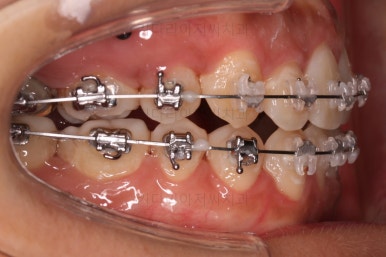

초진 시 입안의 모습입니다.

그냥 봐도 뭔가 애매함이 있죠?

중앙선이 맞지 않고, 교합이 떠보이는 양상이네요.

윗니는 좌측 작은 어금니가 한 개 모자랐고 아랫니는 앞니 하나가 모자라네요.

그런데 앞니는 아랫니가 1개 모자란 채로 교합이 맞춰져서 윗니가 하나 부족한 채로 애매한 상태였어요.